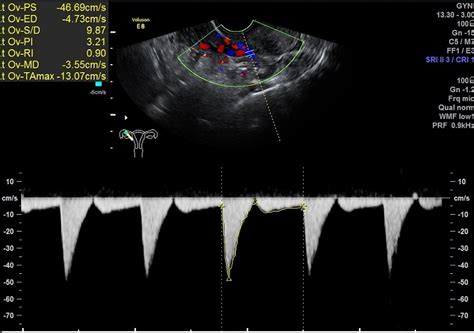

彩超检查收费项目的标准取决于所检查的项目以及检查的部位,所以不同部位收费是不一样的。复一般子宫附件的B超费用大概是一百多块钱,